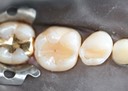

Wes Sato #4-5 try in

Wes Sato #4-5 finish